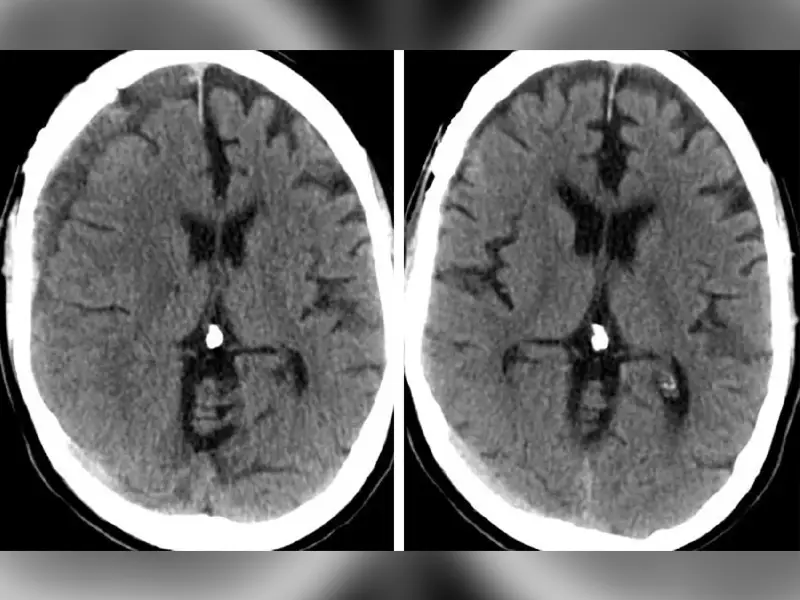

NEJM Study Highlights MMA Embolization Effectiveness For Subdural Hematomas

Subdural hematomas are common, and, by 2030, surgical evacuation for this condition is expected to be the most prevalent cranial neurosurgical procedure. The EMBOLISE (Embolization of the Middle Meningeal Artery With ONYX™ Liquid Embolic System in the Treatment of Subacute and Chronic Subdural Hematoma) study highlights the effectiveness of adjunctive middle meningeal artery (MMA) embolization in treating subdural hematomas. This multicenter trial was led by Jared Knopman, M.D., director of cerebrovascular surgery and interventional neuroradiology at NewYork-Presbyterian and Weill Cornell Medicine, who has been a pioneer of the procedure. Results demonstrated that the combined procedure significantly reduced the risk of hematoma recurrence or progression requiring reoperation compared to surgical evacuation alone. These findings point to adjunctive MMA embolization as a potential new standard of care for patients with subdural hematomas requiring surgical intervention.